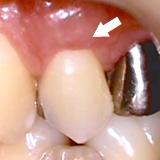

歯槽膿漏・X線写真 | ||

| 歯槽膿漏によって失われた骨(→印の部分)が再生しています。 | ![]() |

【術前】 |

【術後】 |